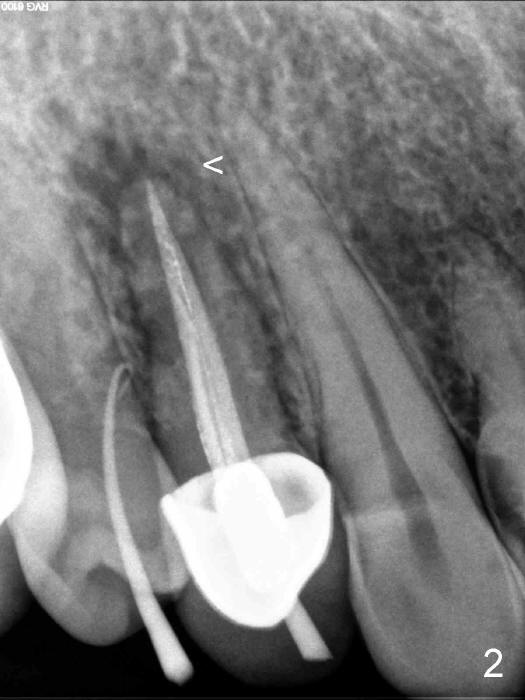

A 60-year-old man has had a fistula for several months (Fig.1,2). Plan A is to place a SM implant (4.5x14 mm, Fig.3), cemented abutment and immediate provisional. After atraumatic extraction, a 2 mm pilot drill is used to create osteotomy at the depth of 14 mm, followed by 2.5 and 3.0 mm reamers at the same depth and insertion of 4.5 mm tap drill with slow handpiece to determine whether there is enough stability. If yes, place the implant mentioned above. If not, use a longer implant. Do you have a 18 mm bone-level implant (UF)? If not, I will bring a 4.5x20 mm gingiva-level tapered or straight implant.

The socket of an upper first premolar is oval (Fig.5), whereas majority of implants are rounded. It is always a mismatch. An implant that matches the shape of the socket most closely is "D" Plateau Implant (Fig.5 insert, Fig.6). The D implant that is appropriate for your case is called D2. It is 20 mm long (Fig.4). On cross section is 5.5 mm wide and 3.5 mm tall at crest (widest portion, Fig.6 insert). The D implant is tapped in. Immediate provisional can be installed. Are you interested in the D implant? Crown forms are needed for the provisional.